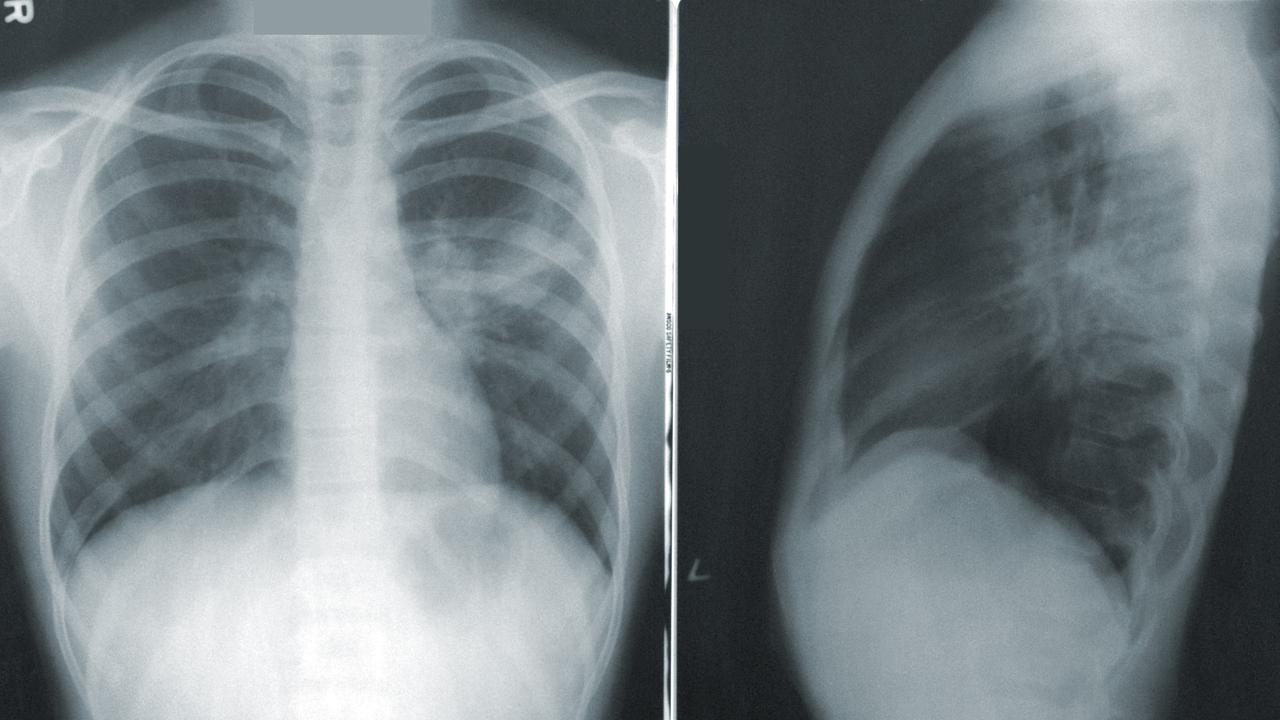

"Hasil ronsen di UGD menunjukkan bahwa dia menderita 'pneumotoraks bilateral', yang berarti kedua paru-parunya kolaps," tulis laporan tersebut.

Menurut National Institute of Health, paru-paru kolaps (Pneumotoraks) terjadi ketika udara bocor dari paru ke ruang antara paru-paru dan dinding dada, yang memberi tekanan pada paru-paru dan mencegahnya berkembang dengan baik.

Adapun perawatan untuk pasien pneumotoraks, menurut Mayo Clinic, biasanya dokter memasukkan alat seperti jarum ke tulang rusuk untuk menghilangkan udara berlebih dari sekitar paru-paru pasien. Maka dalam kasus wanita tersebut, dokter pun menggunakan instrumen tersebut untuk mengeluarkan udara di sekitar paru-paru kanannya. Paru-paru kirinya tidak dirawat karena hanya sebagian kecil saja yang rusak dan dokter mengira kemungkinan besar akan sembuh dengan sendirinya.

Empat minggu kemudian, kedua paru-parunya telah membesar kembali ke ukuran normalnya, dan ia tidak mengalami komplikasi paru-paru lainnya, tulis laporan tersebut.